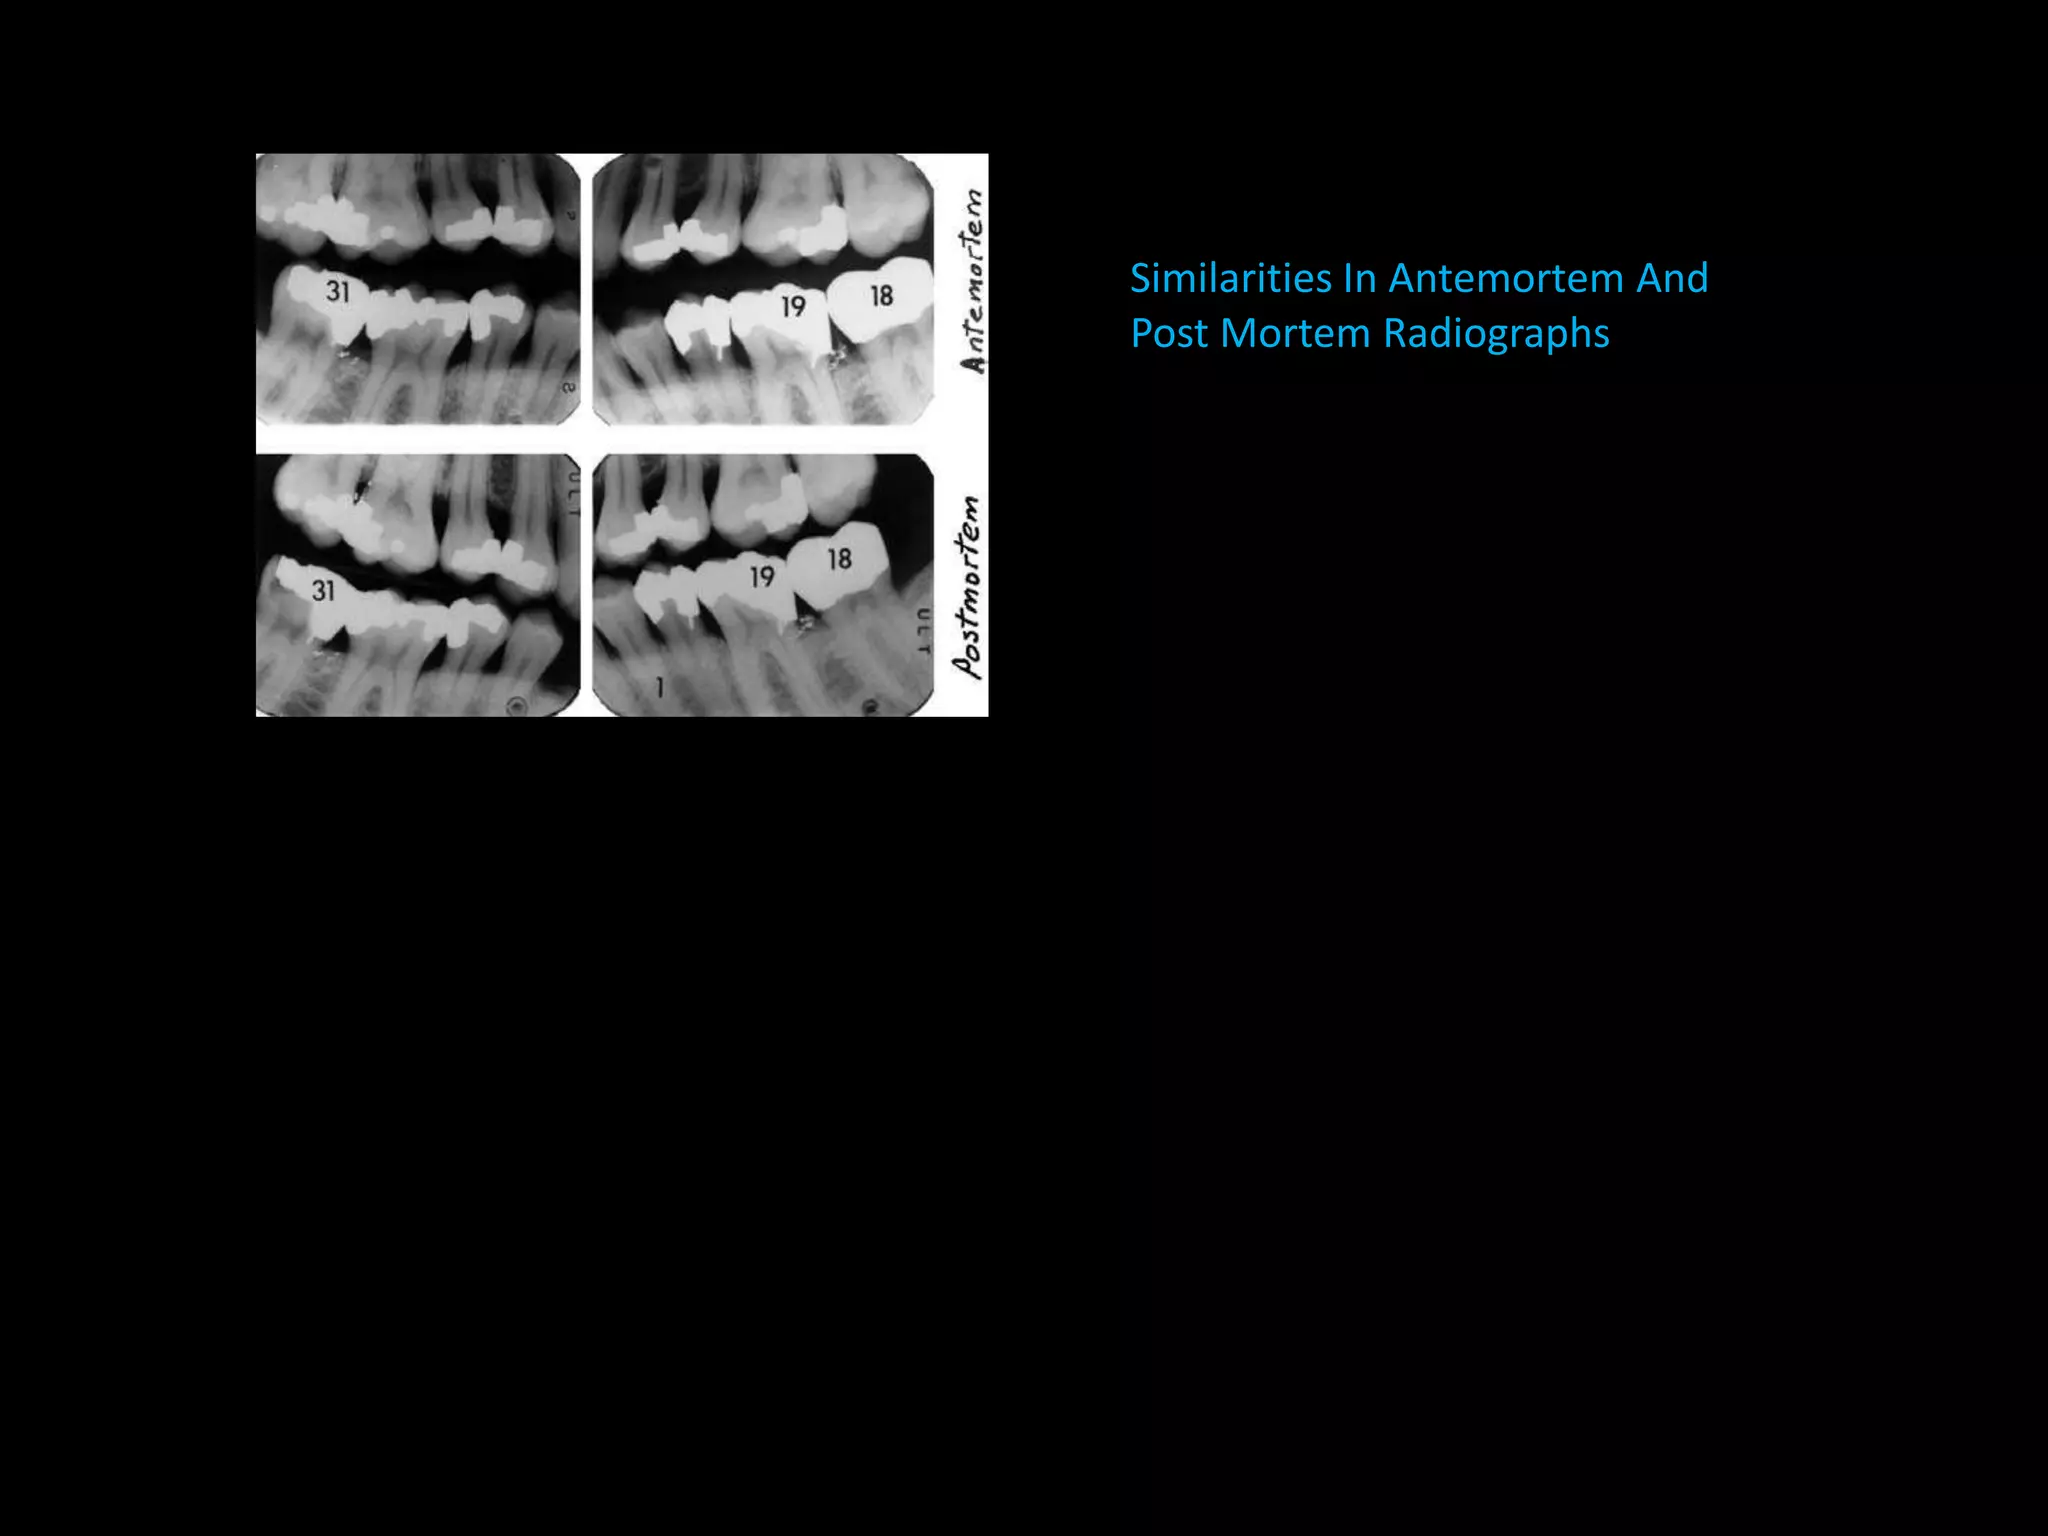

C. COMPARING POST – AND ANTE-MORTEM

DENTAL RECORDS

– Compared by written notes, Study casts, radiographs,

Photographs etc.,

– Criteria for comparison are

a Tooth characteristics [number, eruption status,

position]

b. Personal characteristics

[crown morphology - occlusal ridges, cusps,

Root morphology - branching pattern, furcation,

fusion]

c. Complexity factors – tubercles, pits, additional

ridges, grooves, fissures &

d. Acquired features – hypoplasia, trauma, function,

personal habits, restorations

– Individual with multiple dental treatment & unusual

features – better identified.

– Dental record considered a legal document

– Radiographic identification is often conclusive.